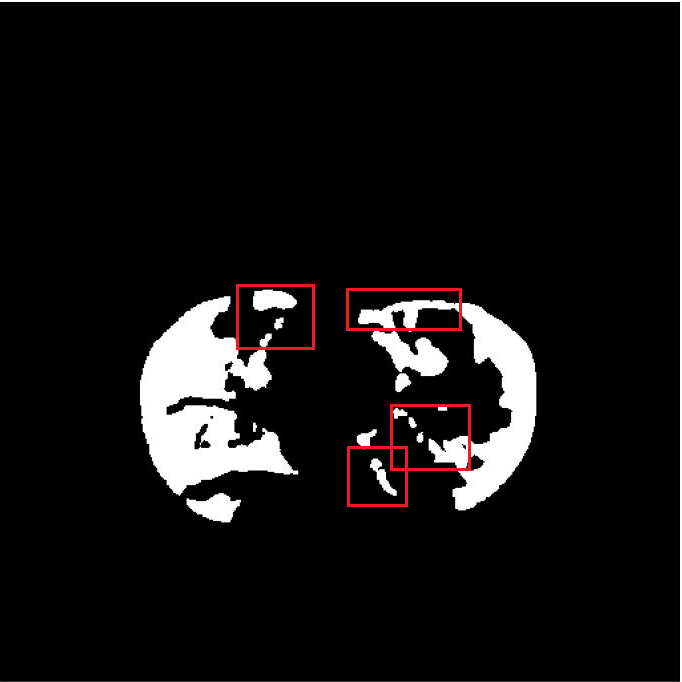

(b) Ground Truth

The resultant segmentation map of FuDSA-Net is observed to be relatively more accurate and closer to the corresponding ground truth, as illustrated in Fig. 3.